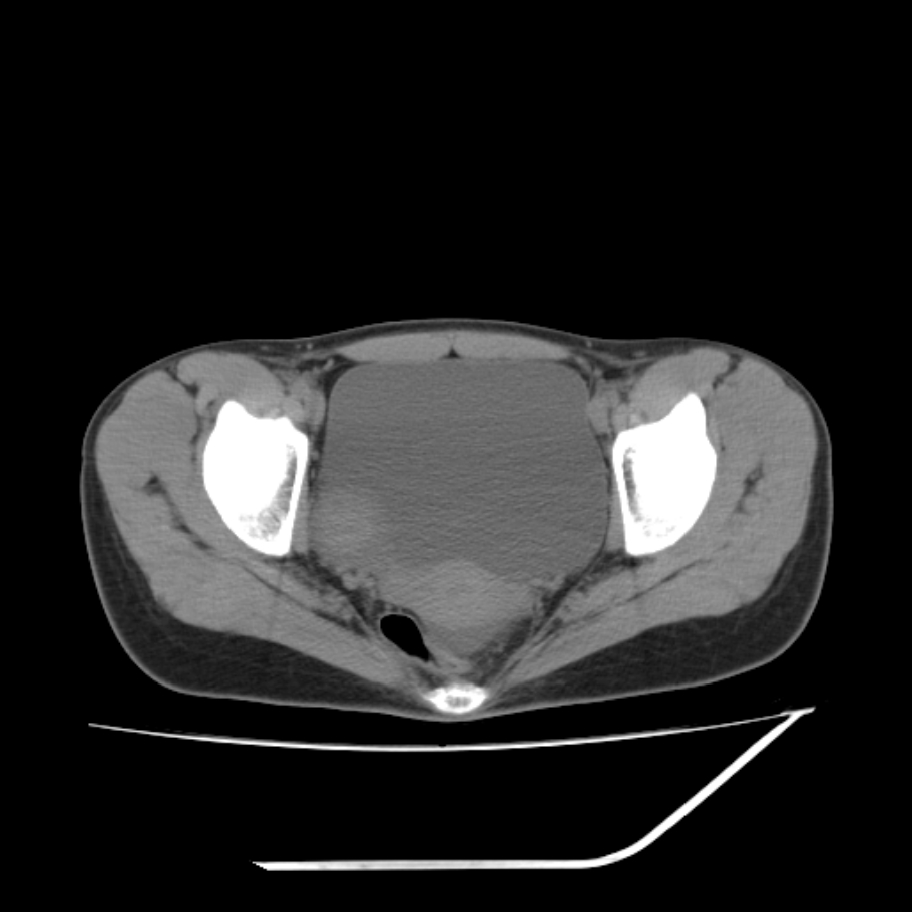

女,25岁。偶尔有右下腹不适感,余无明显异常。(结婚半年),囊壁较厚,是卵巢囊肿吗?

右侧卵巢区椭圆形囊性肿物,内壁光滑 无分隔。直肠子宫间隙内有少量积液征象。结合临床考虑卵巢巧克力囊肿,还要问问有没有痛经,本例ct怎么没有灌肠?要是灌肠或前一前口服造影剂,起码可以和肠管区别开

右侧囊性占位,1囊肿,2囊腺瘤。

考虑右侧卵巢囊性占位性病变(巧克力囊肿?),盆腔积液有不排除宫外孕可能,请结合临床和b超。

右侧卵巢囊伴盆腔少量积液。